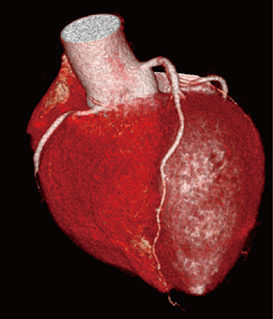

図3 冠動脈撮影 100kVによるFlash撮影